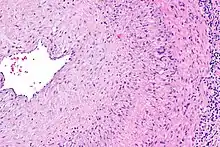

Intermediate magnification micrograph showing giant cell arteritis in a temporal artery biopsy. The arterial lumen is seen on the left. A giant cell is seen on the right at the interface between the thickened intima and mediaH&E stain

The gold standard for diagnosing temporal arteritis is biopsy, which involves removing a small part of the vessel under local anesthesia and examining it microscopically for giant cells infiltrating the tissue.[23] However, a negative result does not definitively rule out the diagnosis; since the blood vessels are involved in a patchy pattern, there may be unaffected areas on the vessel and the biopsy might have been taken from these parts. Unilateral biopsy of a 1.5–3 cm length is 85-90% sensitive (1 cm is the minimum).[24] Characterised as intimal hyperplasia and medial granulomatous inflammation with elastic lamina fragmentation with a CD 4+ predominant T cell infiltrate, currently biopsy is only considered confirmatory for the clinical diagnosis, or one of the diagnostic criteria.[11]